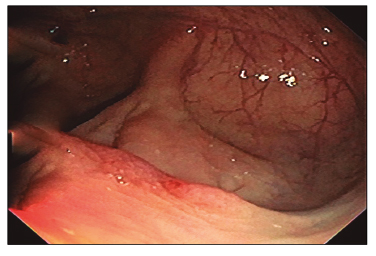

Se realizó un control endoscópico a los 9 meses en el primer caso (Figura 17), y a los 4 meses en el segundo caso (Figura 18) sin evidencia de complicaciones.